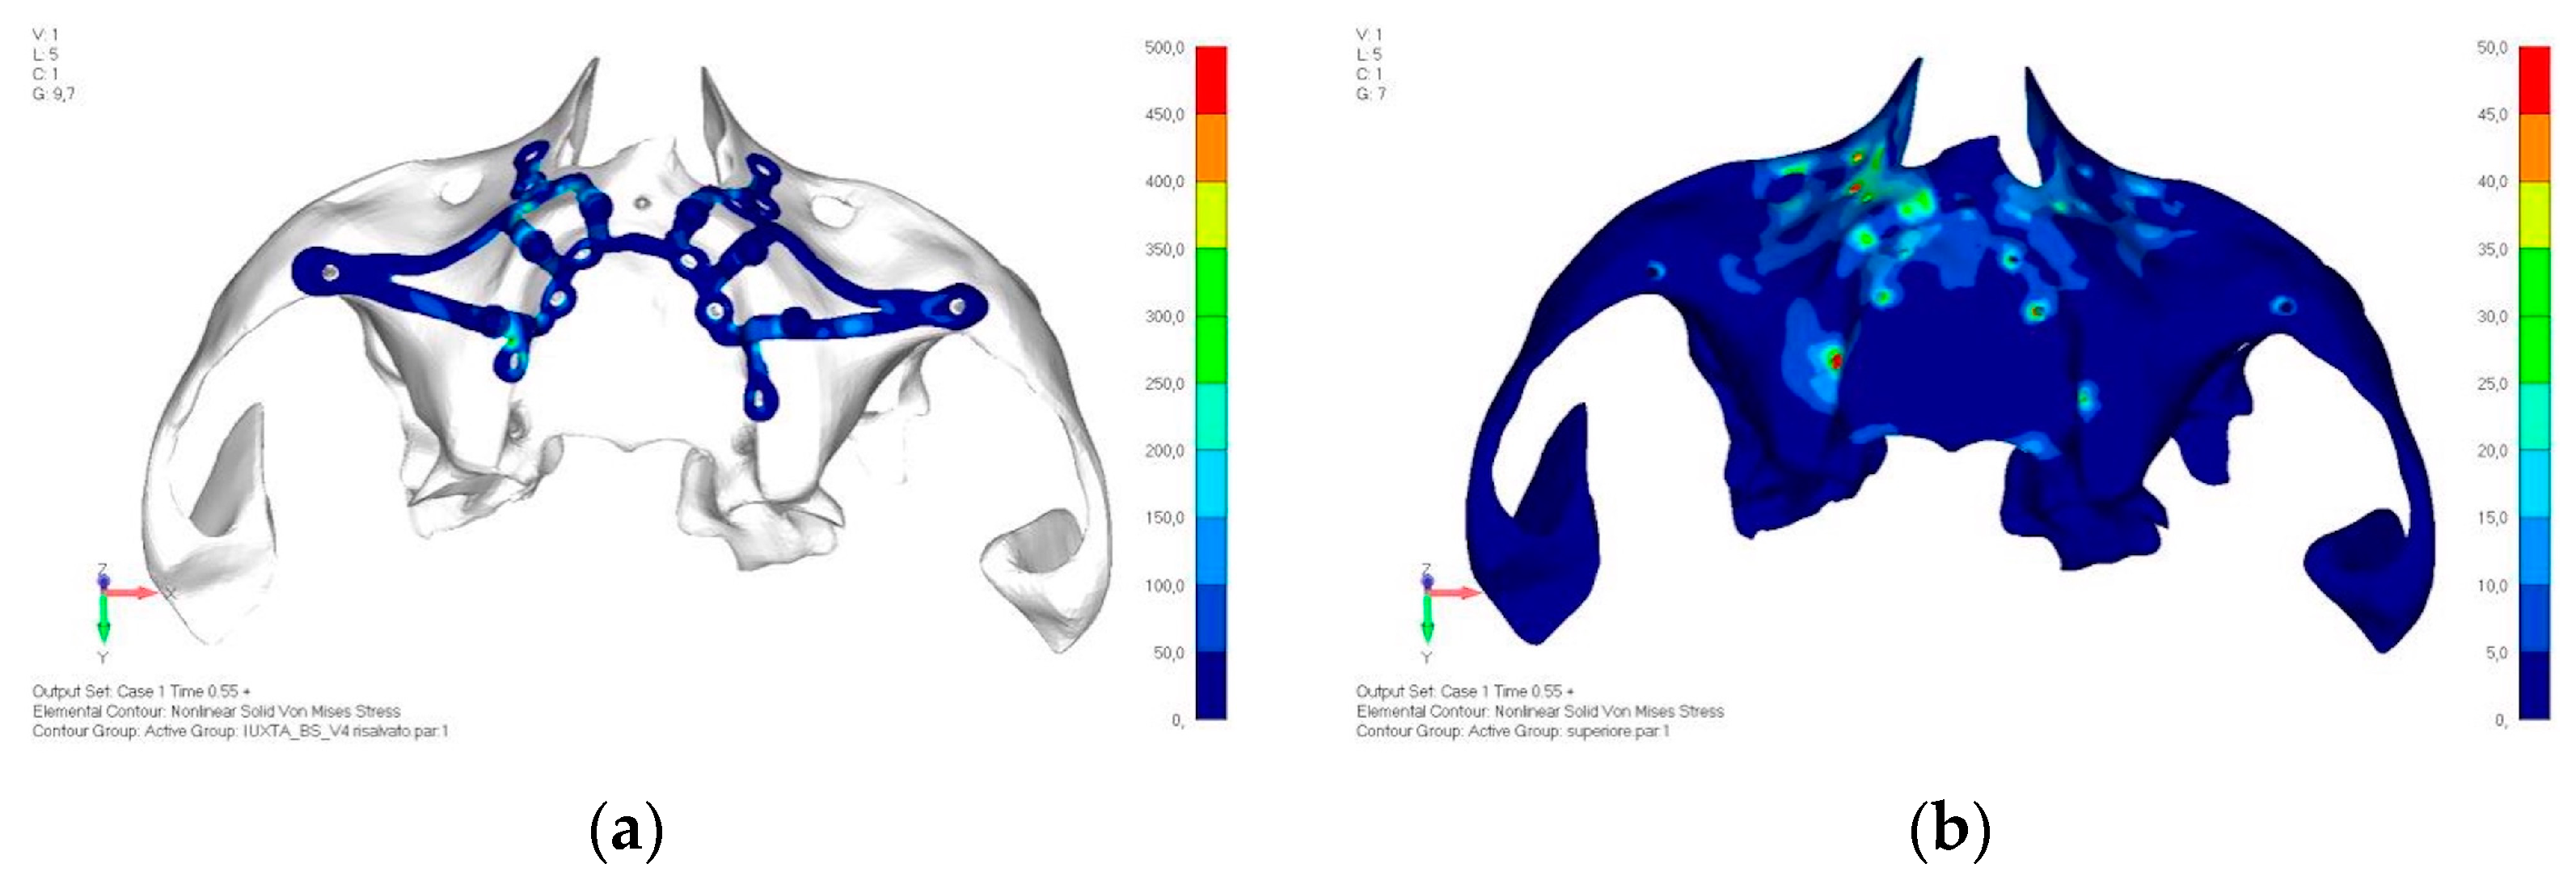

- Model V4. The previously added screw was relocated towards the frontal process, aligning it vertically with the other screws and ensuring that both arms of the first and second abutments connect to this screw (Figure 14). This solution proved to be more effective than V3; the addition of the screw reduces the stress on the other screws and on the support. The area where stress exceeds 50 MPa in the vicinity of the screws is now more contained, and the crestal support shows stresses between 30 and 35 MPa, which are absolutely acceptable (Figure 15a,b).